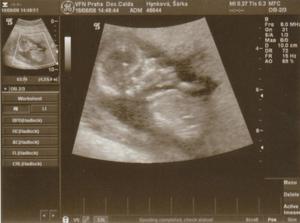

21.7. - dle UTZ 9+2, máme ruce, nohy, hlavu a tělo, vypadáme jak medvídek se svatozáří 🙂 + 1. foto. Vystaveny žádanky na genetiku,krev, NT screening...